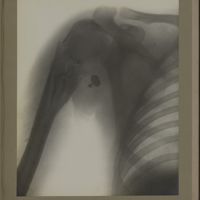

0116 - Page 4 - [Radiographie du thorax et de l'épaule]0116 - Page 4 - [Radiographie du thorax et de l'épaule]

0122 - Page 10 - [Radiographie de l'épaule et du thorax]0122 - Page 10 - [Radiographie de l'épaule et du thorax]

0123 - Page 11 - [Radiographies de l'épaule]0123 - Page 11 - [Radiographies de l'épaule]

0154 - Page 42 - [Radiographie de l'épaule]0154 - Page 42 - [Radiographie de l'épaule]

0170 - Page 58 - [Radiographie de l'épaule]0170 - Page 58 - [Radiographie de l'épaule]

0172 - Page 60 - [Radiographie de l'épaule et du thorax]0172 - Page 60 - [Radiographie de l'épaule et du thorax]

0194 - Page 82 - [Radiographie de l'épaule]0194 - Page 82 - [Radiographie de l'épaule]